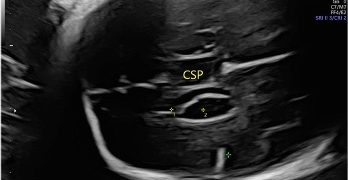

Casi del Mese di Dicembre 2024

Cari soci, finalmente on line le soluzioni dei casi del mese di Dicembre. Grazie a Sara Zullino e Mara Albanese!! Caso 1 - video [pdf-embedder url="https://www.sieog.it/wp-content/uploads/2024/12/Casodelmese_Dicembre2024caso-risposte_gineco.pdf"...